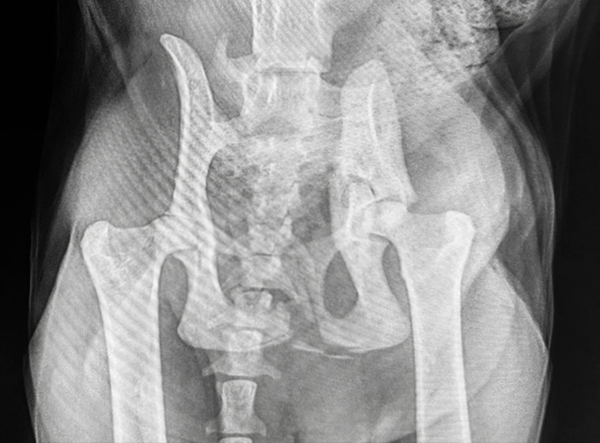

This feline patient presented with a severe pelvic trauma following high-impact trauma. Diagnostic imaging revealed a comminuted ilium and acetabulum fracture, along with sacroiliac (SI) luxation — a complex orthopedic challenge requiring careful reconstruction and stabilization.

Veterinary surgeon Dr. Matan Or (Israel) performed the repair using components from the LeiLOX 1.5 Locking Plate System, known for its precision, flexibility, and lightweight titanium construction.

Positioned on the ilium, the Y-Plate was used to stabilize the comminuted ilial fracture and restore acetabular alignment. The plate’s geometry allowed for secure multi-point fixation in challenging anatomy. - Twisted Straight Plate

A LeiLOX Locking 1.5 straight plate was carefully twisted and adapted to the curved contour of the ilium, providing additional stabilization of the ilial shaft. - Single Transarticular SI Screw

On the contralateral ilium (left side), a long cortical screw was placed across the SI joint into the sacrum to address the sacroiliac luxation. This achieved rigid fixation of the pelvis to the vertebral column.